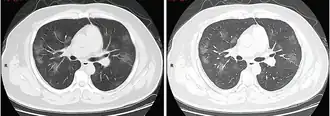

Tomografia computadorizada do tórax

Às vezes, tomografias computadorizadas (TC) do tórax podem ajudar a identificar e caracterizar o estado patológico pulmonar e produzir achados inespecíficos com a infecção por COVID-19. Um estudo descobriu que a sensibilidade da tomografia computadorizada para infecção por COVID-19 era de 98%, em comparação com a sensibilidade da RT-PCR de 71%. No entanto, o teste foi realizado em Wuhan, na China, e, por isso, pode não ser generalizado.[25][26] Grande parte dos achados consistia na presença de opacificação em vidro fosco na região subpleural e pavimentação em mosaico. Esses achados são inespecíficos, pois também são encontrados em outros tipos de pneumonia. Nenhum estudo avaliou, ainda, a precisão e o valor discriminatório das tomografias para distinguir a COVID de outras pneumonias virais.[27][28]

Achados típicos através da TC

Achados típicos através da TC Progressão de achado através de TC

Progressão de achado através de TC